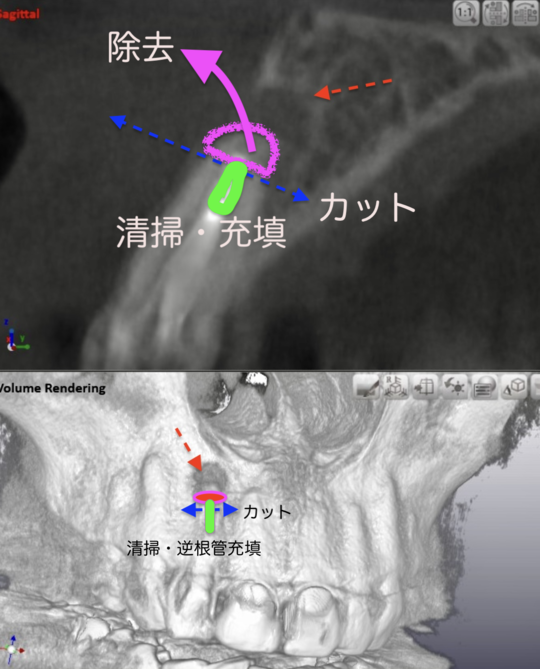

精密根管治療(自費根管治療)治療開始

精密根管治療(自費根管治療)、治療回数2回、治療期間約2週間、治療費6万8千円+4,500円X1回

歯肉への切開が必要です、ウミの袋も取り出します

術直後レントゲン写真

外科的歯根端切除術逆根管充填(自費根管治療)、治療回数2回、治療期間約2週間、治療費6万8千円+4,500円X1回 ジルコニアクラウン(審美的前歯用)14万円

外科的歯内療法は、通常の歯の中から行う一般的な根管治療だけでは治りが望めなかったり、それの経過が悪い場合や被せ物を外せず一般的な根の治療が行えない場合に行います。根尖病変(根の先の周囲の炎症)はバイ菌が原因であることを考えると、まずは、通常の治療で根管内を清掃充填治療してから行った方が確実です。大きな副作用はありませんが、外科的処置が特徴であり、たまに切開線が歯茎に残ることがあります。確実に処置できれば90%以上の確率で治癒します。今回の症例は期間的制約から2段構えの治療計画で行いました。